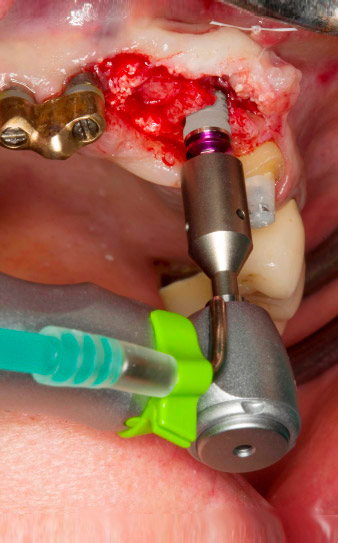

Pilotbohrung mit dem neuen Implantmed und dem Winkelstück WS-56 L

Abb. 2: Zwei Monate später erfolgt die Pilotbohrung mit dem neuen Implantmed und dem Winkelstück WS-56 L (Programm P1, Übersetzung 1:1). Die Kühlung erfolgt über das links positionierte Sprayrohr (für Rechtshänder).